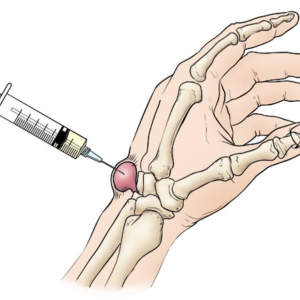

Ganglion Cyst